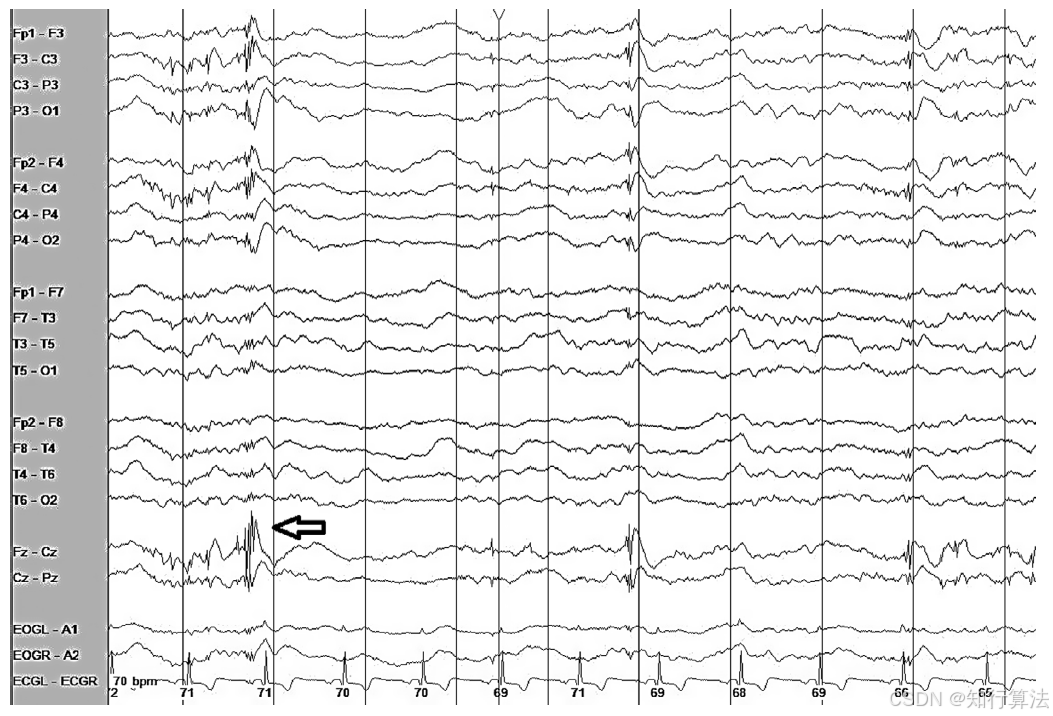

产生原因:心脏电活动经容积导体传导至头皮电极,尤其在耳参考导联明显。

波形特征:周期性尖波,与心电图QRS波严格对应(图15:弥漫性“周期性”伪迹,后头部明显)。

临床意义:可能误认为周期性放电。起搏器伪迹出现在QRS前极短时程。

处理方法:同时记录心电图通道,对比识别。

图15:出现与 QRS 波群相对应的弥漫性“周期性”心电图异常波形